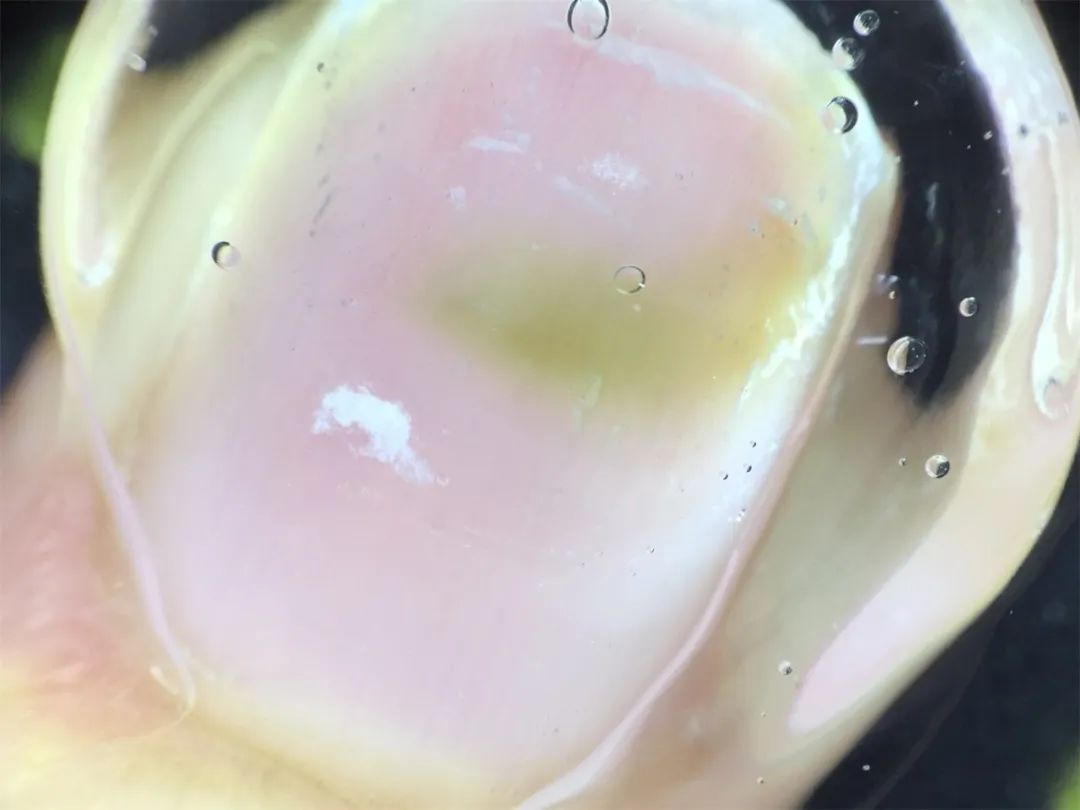

(皮肤镜下的指甲)

“铜绿假单胞菌感染。”经过检查检验,皮肤科朱定仙医师告诉笑笑,她的指甲变绿色是由于一种叫铜绿假单胞菌的细菌感染,并在她指甲上“安家”繁殖,导致细菌的产物绿色素进入甲板呈现绿色现象。